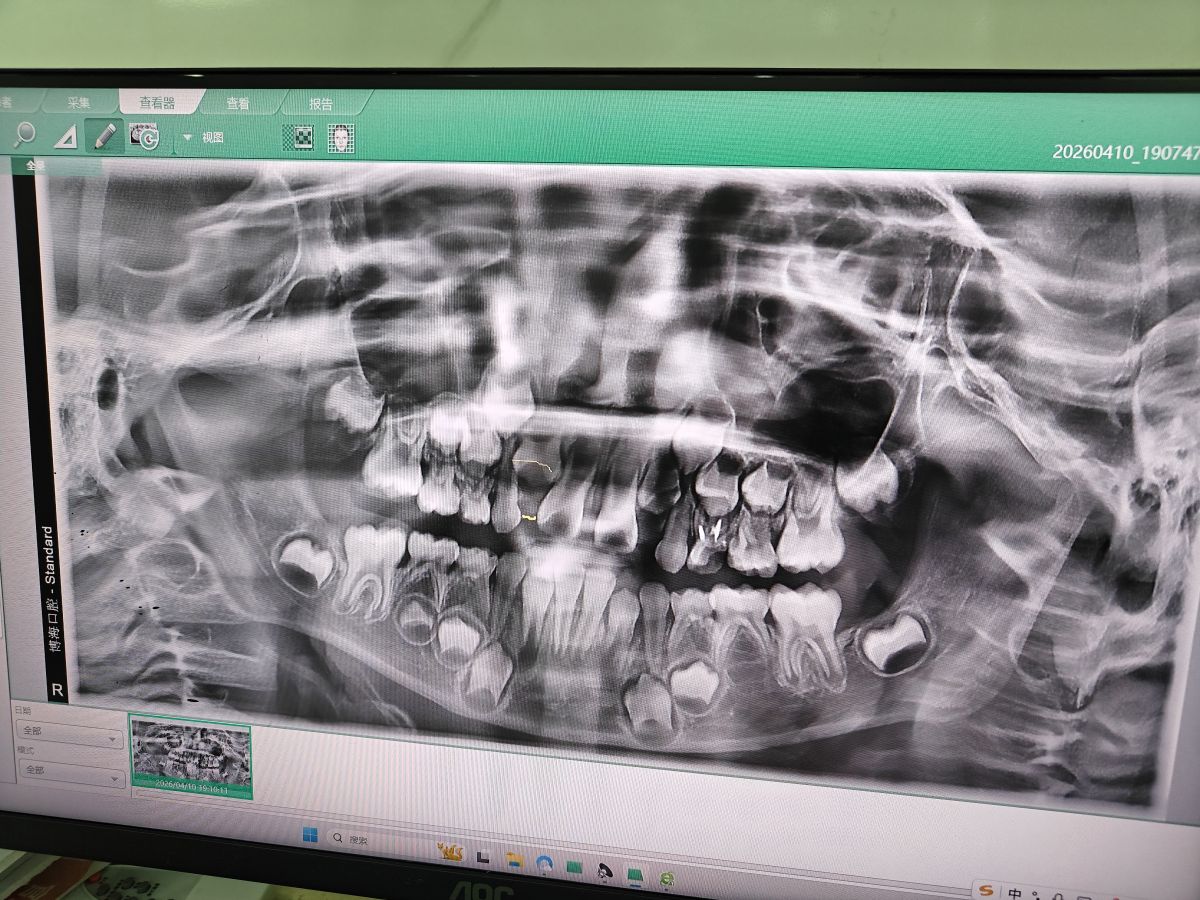

isyeung 又去看牙医🦷